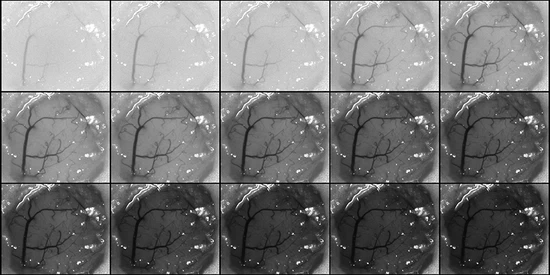

We are designing and building translational laser speckle contrast imaging systems for clinical applications such as continuous blood flow monitoring during vascular neurosurgery.